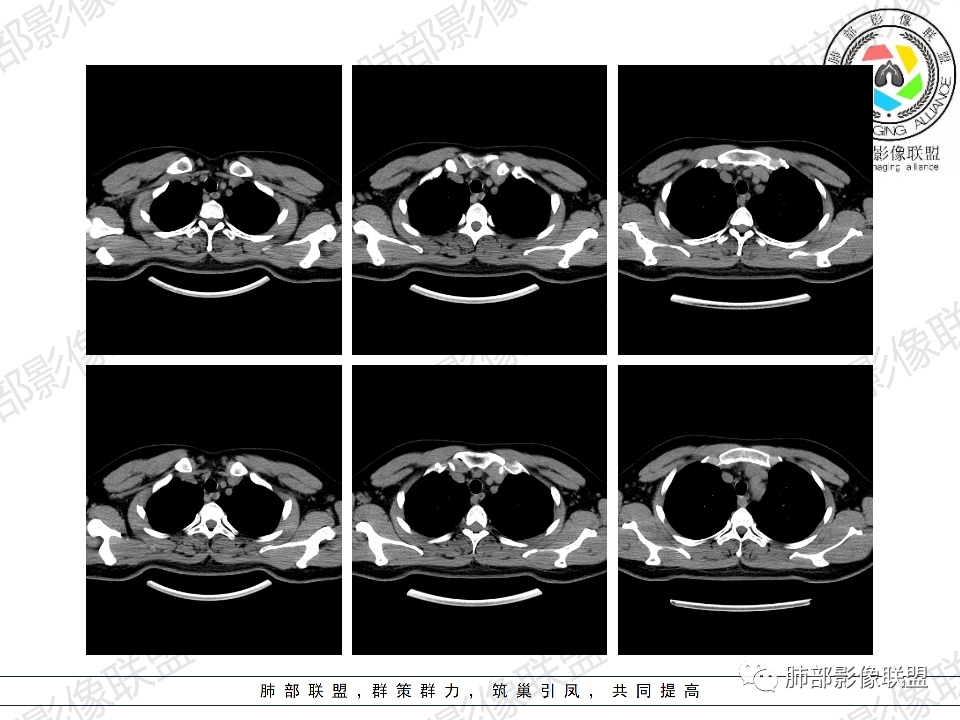

年轻男性,有HIV病史,免疫力缺陷病史,CD4明显减低,左肺胸膜下多发大小不等结节影,部分侧向融合,平行于胸膜,周围伴有模糊的GGO,部分结节与血管相连,血管束增粗,考虑隐球菌,建议查隐球菌荚膜实验,脑脊液隐球菌荚膜,鉴别:CMV(局限性比较少见)

年轻人,男性,HIV阳性,双肺多发斑片状,结节状阴影,以胸膜下分布为主,病灶与支气管血管束垂直生长,周围可见磨玻璃影,考虑肉芽肿病变,隐球菌感染可能性大,鉴别GPA,胞子菌肺炎。

双肺胸膜下多发大小不等结节伴晕征,部分似有融合

左肺多发大小不等结节影,部分融合,胸膜下分布为主,平行于胸膜,周围伴有磨玻璃晕,考虑隐球菌,鉴别:PJP

年轻男性,HIV阳性,胸闷喘憋,双肺胸膜下多发斑片结节影,周围伴晕,部分融合,白细胞低,CD4明显减低,考虑机会性感染性病变,隐球>PCP>结核

青年男性,HIV阳性,白细胞及淋巴细胞显著降低,CRP增高,胸闷气喘一周,影像为双肺胸膜下平行于胸膜分布的多发大小不等结节伴晕,单从影像上看,隐球是要首先考虑,但是不好解释临床症状。需要鉴别:1、曲霉所致IPA,临床有粒缺基础,胸闷一周要考虑,但影像不是典型的血道或气道分布又存疑,2、马尼,CD4低,HIV基础,要考虑,但是否有旅广史?另外纵隔淋巴结无肿大,肝脾不肿大,可能稍小。3、PCP,HIV基础,CD4低,胸闷气喘要考虑,影像分布不典型。4、腺病毒或EB病毒感染,HIV基础,影像改变要考虑,但是发病无发热,存疑。5、结核,临床与影像均不典型。可能小。综上,隐球>曲霉>PCP>马尼>病毒感染。下一步,查隐球荚膜抗原,NGS找病原体。

我们科里读片的时候,也是觉得主诉特别像PCP的主诉。但是影像学表现,双肺胸膜下多发小结节,结节周围带晕,蘑菇兄弟手拉手,有的结节侧向融合整体与胸膜平行。影像符合隐球。我们科里艾滋合并隐球菌真正确诊出来的很少。所以要说总结HIV合并隐球的病例特点,我没有发言权

5、分布:病灶分布多位于胸膜下,可紧贴胸膜,也可与胸膜邻近,病灶长轴与胸膜平行。(划重点,分布特点非常重要)

10、“葫芦兄弟”:邻近胸膜多发结节,形态密度类似,可簇状分布,较少多形性,没有新旧不等。